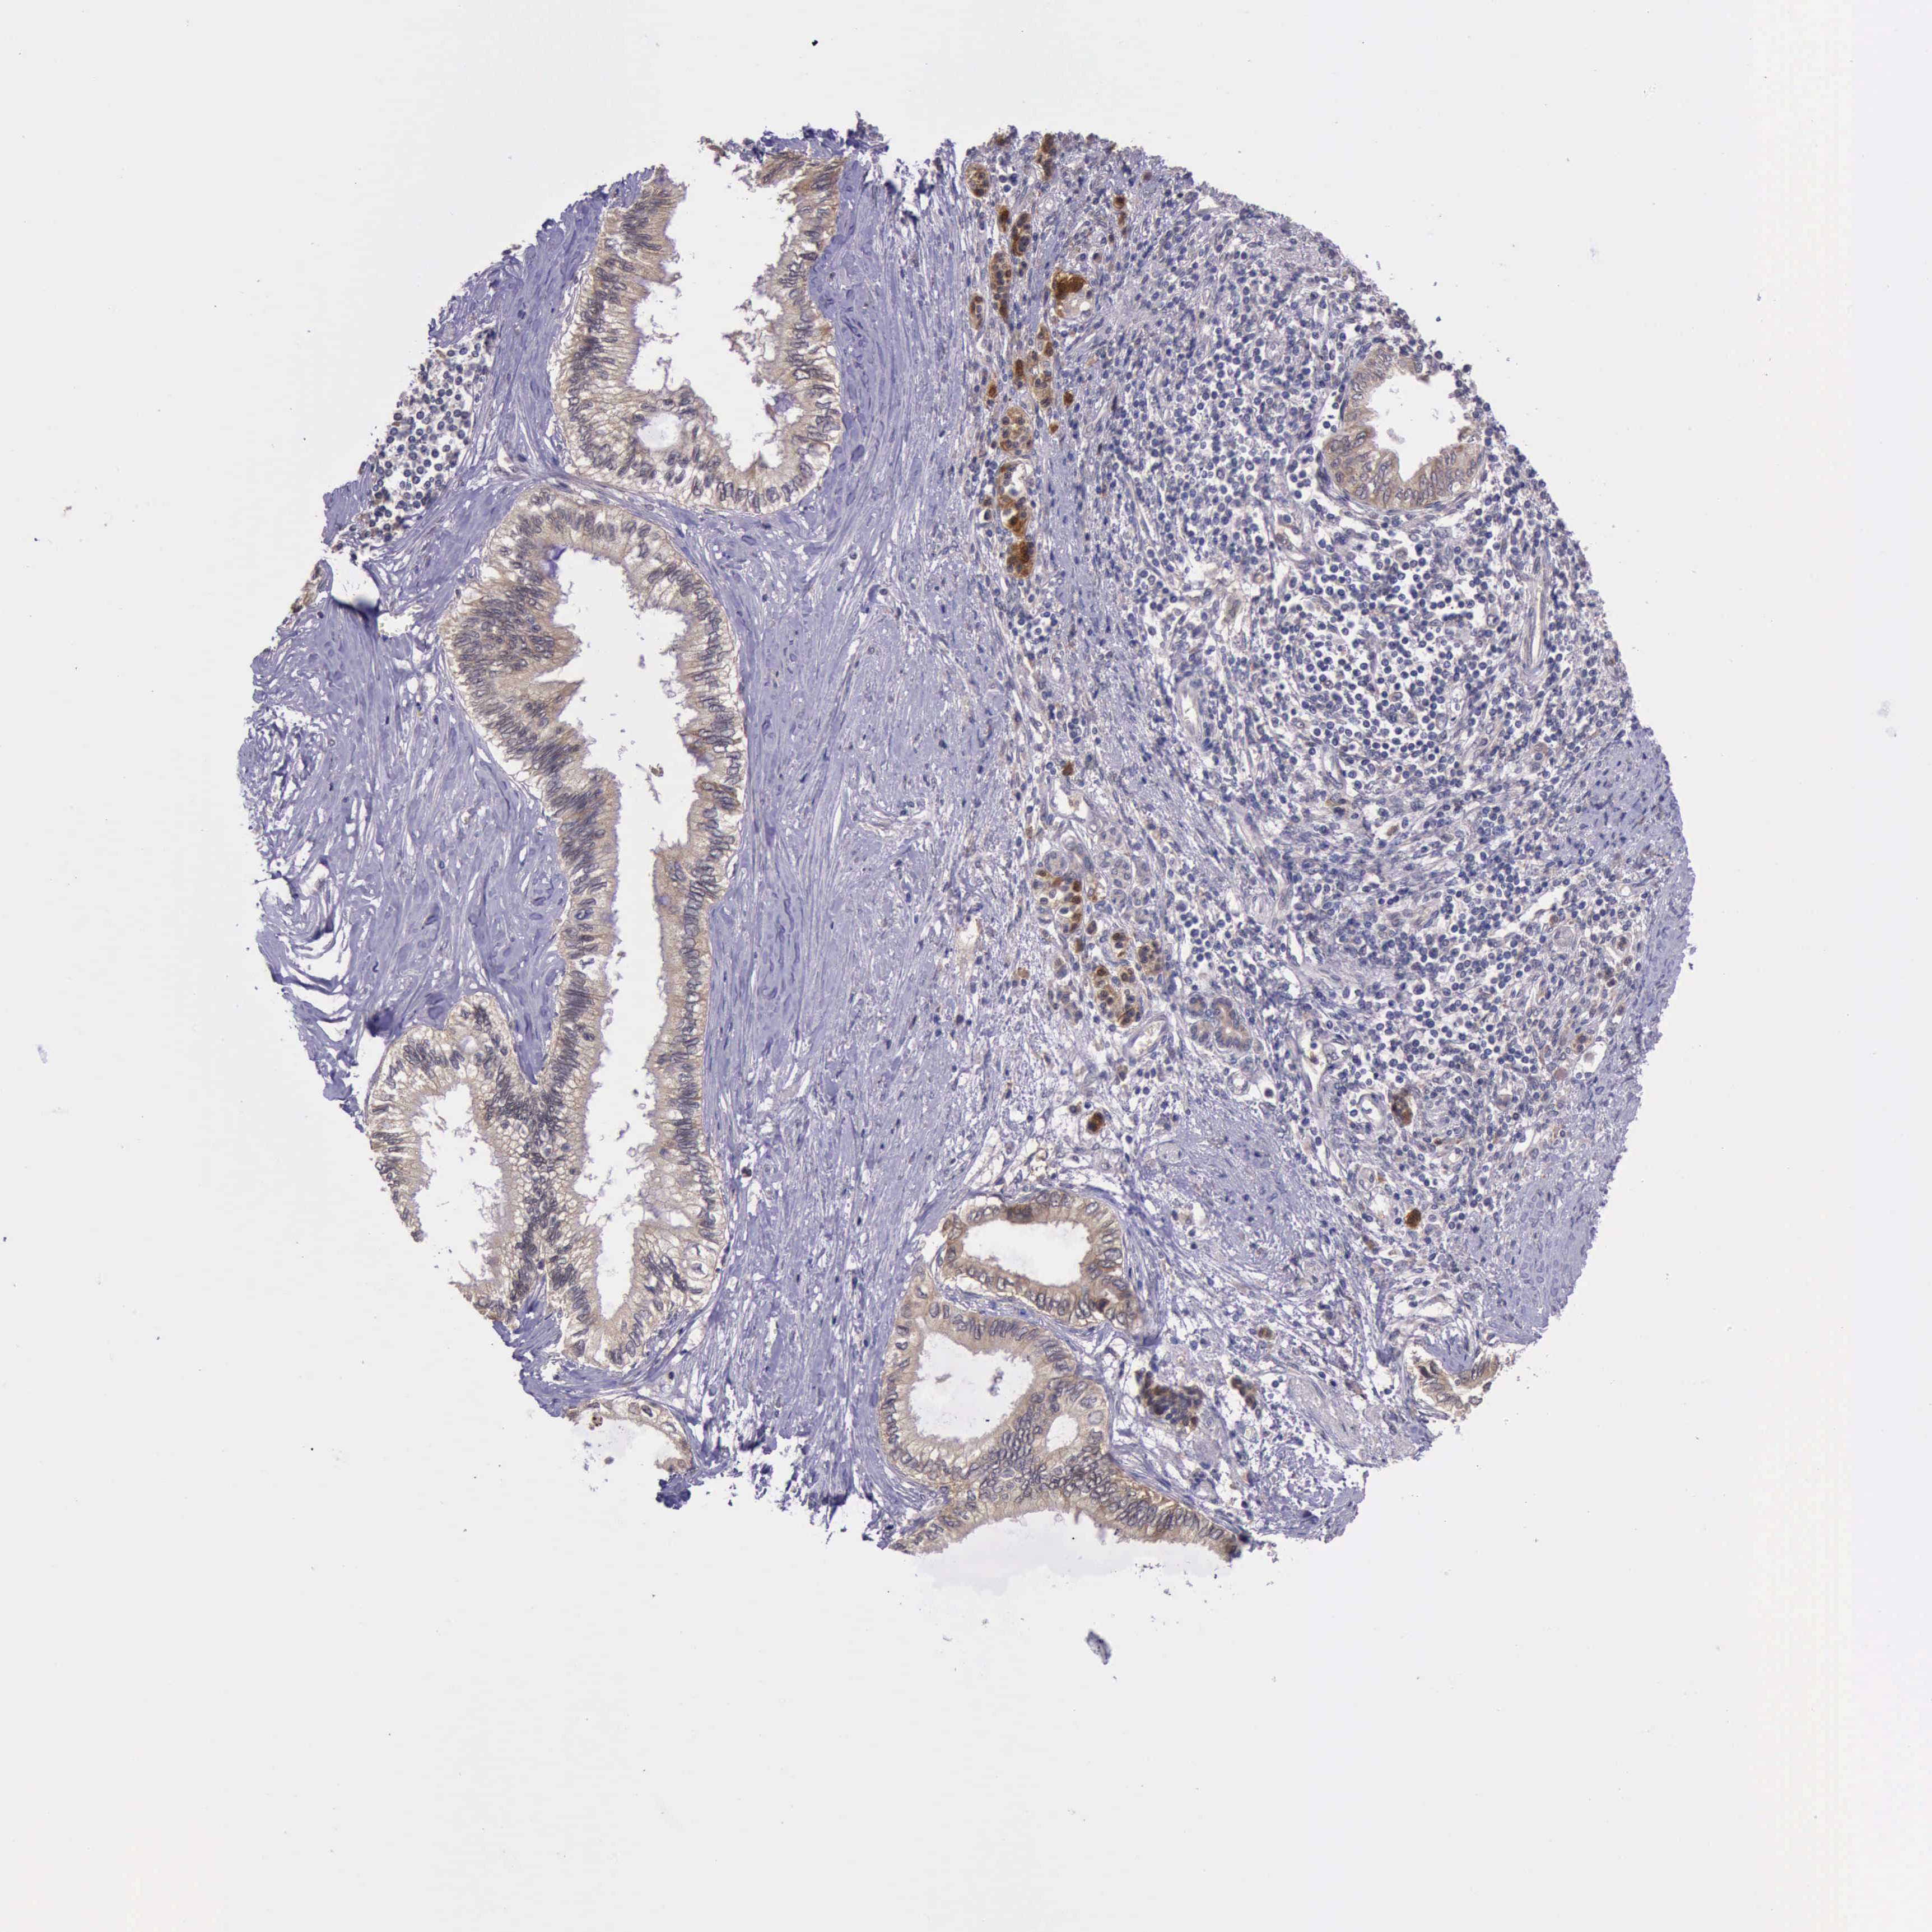

PANCREATIC CANCER - Protein expressioni

A mouse-over function shows sample information and annotation data. Click on an image to view it in a full screen mode. Samples can be filtered based on level of antibody staining by selecting one or several of the following categories: high, medium, low and not detected. The assay and annotation is described here.

Note that samples used for immunohistochemistry by the Human Protein Atlas do not correspond to samples in the TCGA dataset.

Antibody stainingi

Antibody staining in the annotated cell types in the current human tissue is reported as not detected, low, medium, or high, based on conventional immunohistochemistry profiling in selected tissues. This score is based on the combination of the staining intensity and fraction of stained cells.

Each image is clickable and will lead to virtual microscopy that enables deeper exploration of all samples and also displays staining intensity scores, fraction scores and subcellular localization as well as patient and tissue information for each sample.

Antibody HPA001208

Staining

High

Medium

Low

Not detected

Intensity

Strong

Moderate

Weak

Negative

Quantity

>75%

75%-25%

<25%

None

Location

Nuclear

Cytoplasmic/membranous

Cytoplasmic/membranous,nuclear

Adenocarcinoma, NOS